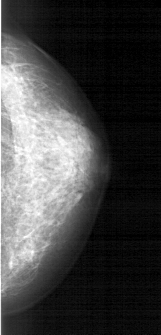

A_1609_1.RIGHT_MLO

RIGHT_MLO LINES 5311 PIXELS_PER_LINE 2131 BITS_PER_PIXEL 12 RESOLUTION 43.5 NON_OVERLAY